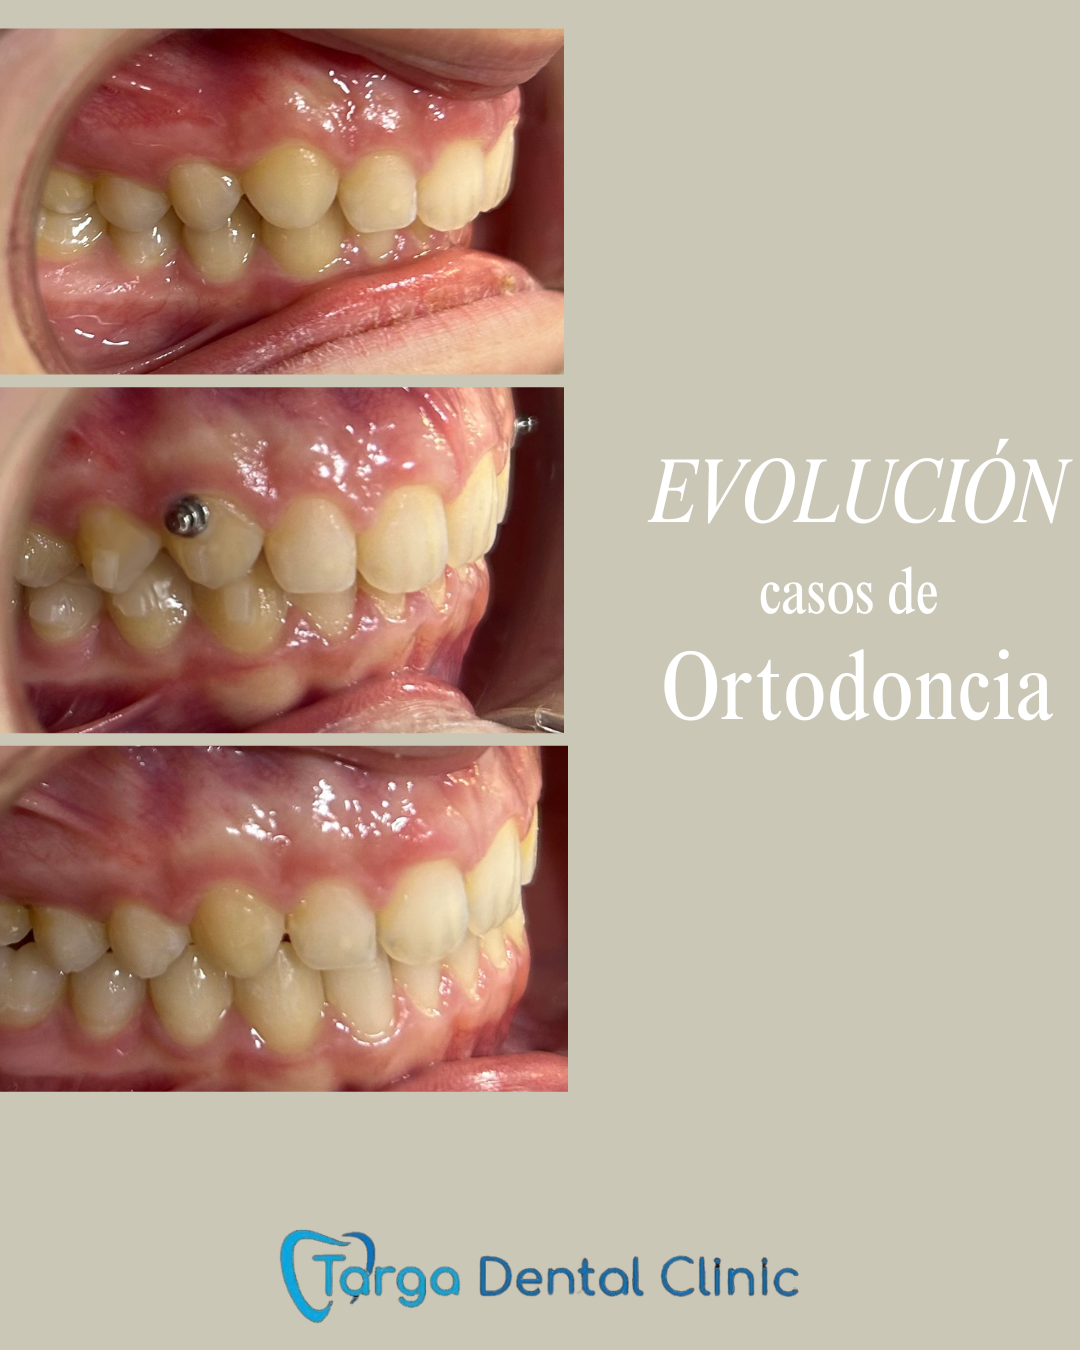

Ortodoncia y Odontopediatría

Ofrecemos tanto ortodoncia invisible con alineadores como ortodoncia fija con brackets.

Evaluamos cada caso y te recomendamos el más adecuado para ti. También ortodoncia para los más pequeños y los pacientes en crecimiento.

Tratamientos realizados en nuestra clínica